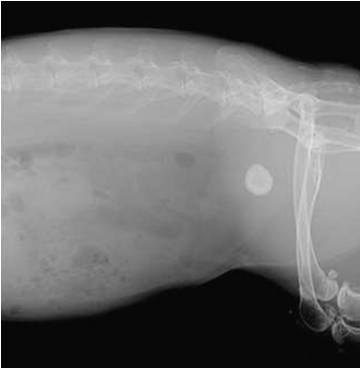

Le diagnostic est relativement aisé par radiographie. Cependant, toutes les sabloses ne sont pas nécessairement pathologiques. Un bilan complet associant prise de sang et échographie est recommandé. Le traitement passe par une amélioration de l'hydratation et des rectifications alimentaires. Cette sablose peut prédisposer aux calculs vésicaux, urétéraux ou rénaux.

Le diagnostic se fait par radiographie mais une échographie et une prise de sang sont recommandés pour exclure la présence d'autres calculs au niveau des uretères et des reins et aussi pour vérifier l'absence d'insuffisance rénale. Le traitement est quasiment toujours chirurgical, certains cas particulier peuvent être traité par endoscopie ou par traitement médical.

Une infection par E.cuniculi peut éventuellement prédisposer à la formation de calculs. Les calculs rénaux se voient généralement à la radiographie mais certains calculs ne peuvent être visualisés que par échographie.